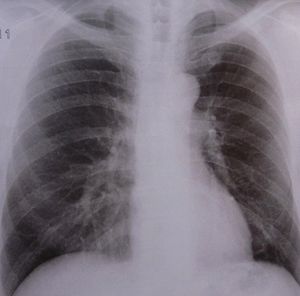

Lunge: Mukoviszidose schwierig zu behandeln (Foto: pixelio.de, Dieter Schütz) |

Der neue Ansatz könnte ein Durchbruch sein. Mukoviszidose-Patienten sterben häufig vor dem 40. Lebensjahr. Schleim sammelt sich in den Lungen an, führt zu einer Schädigung und erhöht damit die Wahrscheinlichkeit einer Infektion. Allein in Großbritannien leidet eines von 2.500 Babys an Mukoviszidose. Von den Eltern geerbte Fehler in der DNA führen zu Schädigungen des mikroskopischen Mechanismus, der die Menge an Salz und Wasser in den Lungenwänden reguliert.

Die Folge ist ein dickflüssiger Schleim, der unweigerlich zur Schädigung der Lungen führt. Antibiotika helfen, Infektionen zu vermeiden. Andere Medikamente können den Schleim lösen. Für das grundlegende Problem gibt es derzeit jedoch keine Behandlungsmöglichkeit. Die Kombination der beiden Medikamente Lumacaftor und Ivacaftor zielt darauf ab, genau dieses Problem zu lösen. Patienten, die 24 Wochen lang beide Medikamente erhielten, verfügten über eine bessere Lungenfunktion.